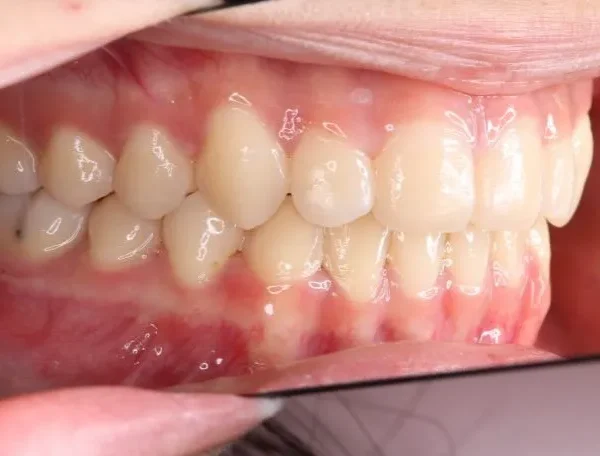

初診時年齢 高校生 (女性) 主訴 歯並びがガタガタ・口元の突出感

診断名 叢生・開咬・上下顎前突 装置名

特徴 ゆがんで生えている

状態 ガタガタ・でこぼこに生えている(叢生)

受け口(下顎前突/反対咬合)

前歯で噛めない(開咬/オープンバイト)

上下前歯、口元が出ている、口ゴボ(上下顎前突)

ガタガタの歯並びにお悩みの患者様でした。

口唇の突出感の他、下顎面高が長い印象も認められました。

歯科矯正アンカースクリューを用いた治療で、非抜歯で口唇突出の改善、臼歯の圧下、叢生の解消を図りました。

叢生は解消し、口元が大幅に引っ込み、下顎面高も縮小しました。